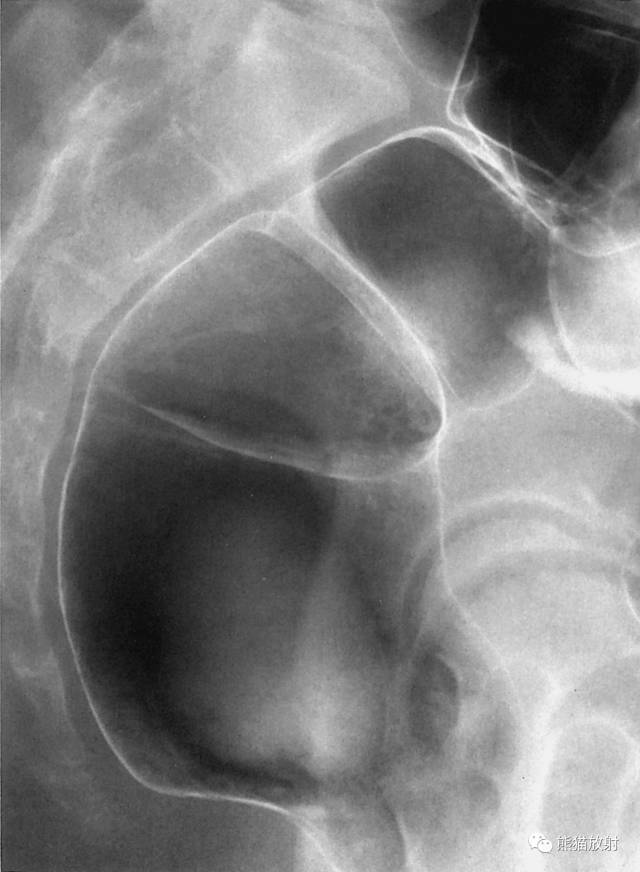

11 Rectum 直肠

1 Rectosigmoid junction 直肠乙状结肠连接部,2 Sacrum 骶骨,3 Retrorectal space 直肠后间隙,4 Transverse rectal fold 直肠横襞,5 Femoral head 股骨头,6 Rectal ampulla 直肠壶腹部,7 Coccyx 尾骨,8 Anorectal junction 肛门直肠交界处